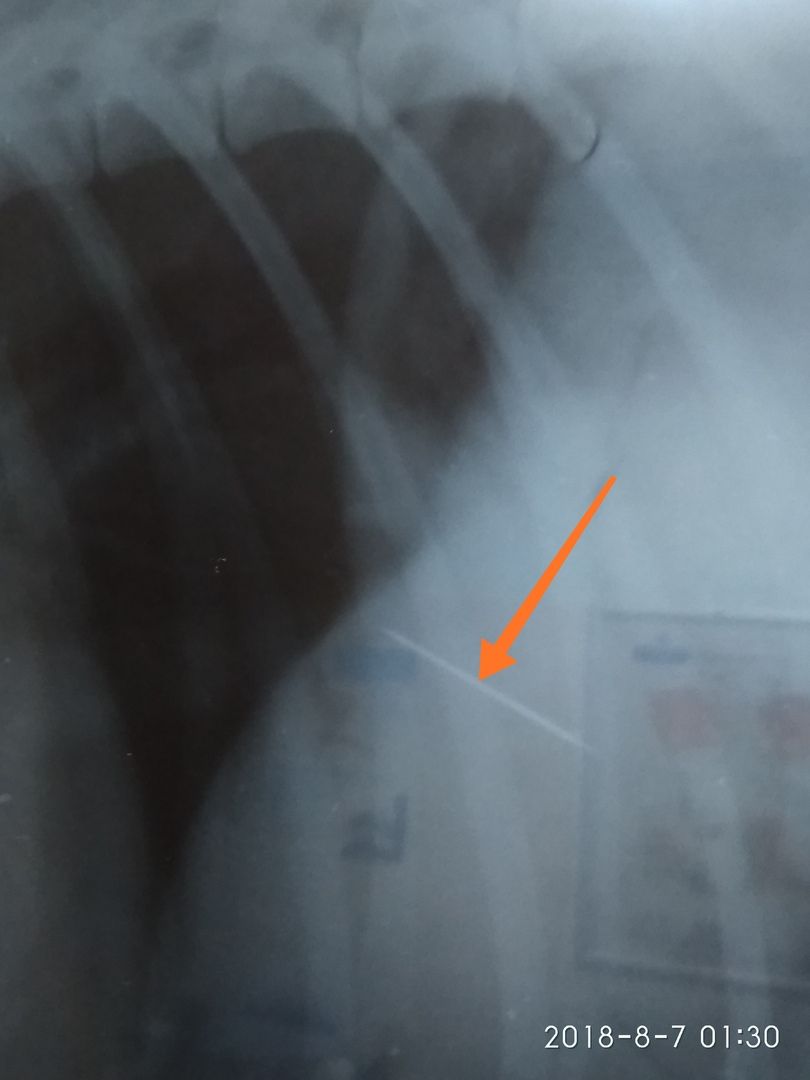

«Будьте аккуратнее, отпуская собачек с поводков! На фото снимок иглы, которая через желудок ушла в печень. Сейчас песик прооперирован, но сам факт...», — пишет знакомая хозяина пострадавшей собаки Полина Зедереева.

По словам девушки, собака наткнулась на приманку с микрорайоне Северном, а хозяину пришлось взять кредит, чтобы оплатить операцию и лечение.

фото: Полина Зедереева